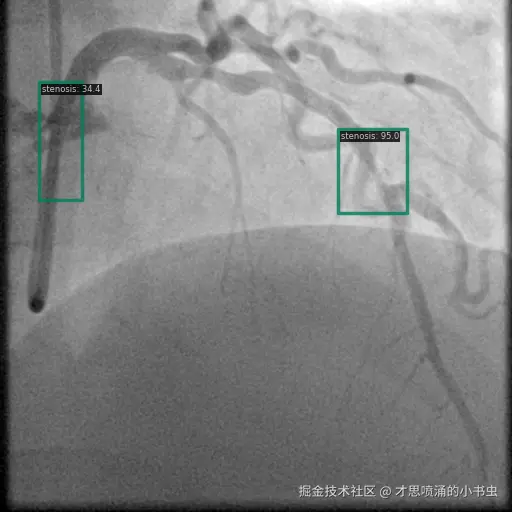

以下图像展示了每个模型在相同冠状动脉造影图像上的表现:

图6 Grounding DINO 的检测显示具有明确标签的高置信度狭窄检测。

Grounding DINO 识别出了更多的区域,但有时由于过度检测导致预测混乱。该模型似乎利用其跨模态理解来检测更广泛的狭窄表现。如图 6 和图 9 所示,Grounding DINO 通常以不同置信度分数检测多个狭窄区域。虽然这增加了捕获所有狭窄区域的可能性,但同时也提升了假阳性的可能性。

图9 Grounding DINO 检测显示多个具有置信度分数的检测区域。